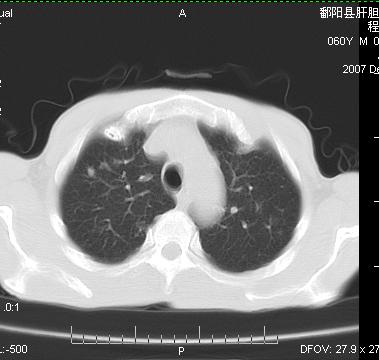

两肺示有散在大小不等类园形边缘不整密增高影.

两肺及胸膜多发性转移瘤。

转移要考虑,但霉菌感染也要排除.

双侧胸壁见多发结节软组织密度灶,两肺内见广泛结节状、面团样影,两肺及胸膜多发性转移瘤。支持

根据:病变确实是多发,但大部分边缘不光滑,欠规整,密度不均匀。也就是说“大部分病灶不是典型转移瘤的表现”。转移瘤可以不典型,但如此大部分不典型,却是很少见的。结合发烧病史,考虑肺多发小脓肿或其他炎性病变,如霉菌等感染!建议痰培养,抗炎治疗后复查!

从病人年龄及肺内表现首先考虑转移瘤,但病人以咳嗽发热胸痛为首发症状还要考虑血行播散型肺脓肿及白血病非内表现等,结合实验室检查有鉴别意义。